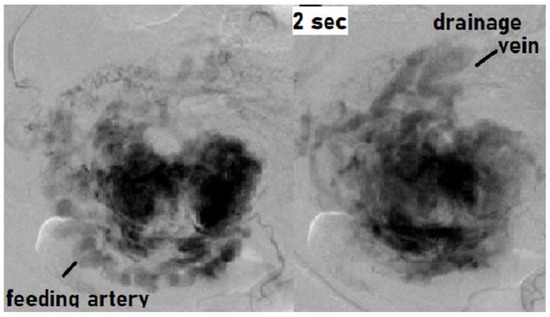

Angiography demonstrated abnormal engorgement in the arterial phase, with a thick venous phase visualized only 2 s later. This indicated the presence of an arteriovenous shunt, and an AVM with a hypervascular region was diagnosed (Figure 2) [20].

Figure 2. Findings of angiography: Abnormal engorgement in the arterial phase, with a thick venous phase visualized only 2 s later. This indicated the presence of an arteriovenous shunt. There was no pulsatile arterial perfusion in the remnant itself, where the contrast agent simply appeared to be leaking.